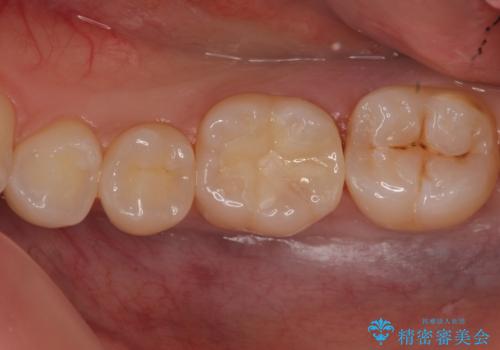

奥歯の虫歯 セラミックインレーによる治療

- 検査をしたところ奥歯に小さな虫歯を発見。

大きくなる前に白い詰め物で治療がしたいとのことでセラミックインレーでの治療になりました。

口の中を見ただけでは異常がないのにレントゲン画像上では虫歯がある、といったことは多々あります。奥歯とはいえ、口をあけると外から見えてしまうため白いセラミックでの治療ができたことを大変喜んでいただけました。